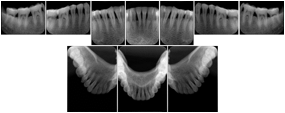

Intra-oral radiography typically involves acquisition of multiple images of various parts of the dentition. Many digital radiographic systems offer customized templates that are used for displaying the images in a study on the screen. These templates may also be referred to as mounts or view sets. The Structured Display Object represents a standard method of encoding and exchanging the layout and intended display of Structured Displays. A structured display object created in this manner could be stored with a study and exchanged with images to allow for complete reproduction of the original exam.

1. A patient visits a General Dentist where a Full Mouth Series Exam with 18 images is acquired. The dentist observes severe bone loss and refers the patient to a Periodontist. The 18 images from the Full Mouth Series along with a Structured Display are copied to a DICOM Interchange CD and sent with the patient to see the specialist. The Periodontist uses the CD to open the exam in his Dental Radiographic Software and consults via phone with the General Dentist. Both are able to observe the same exam showing the images on each user's display using the exact same layout.

Intra-oral Full Mouth Series Structured Display

Figure OO-1. Intra-oral Full Mouth Series Structured Display